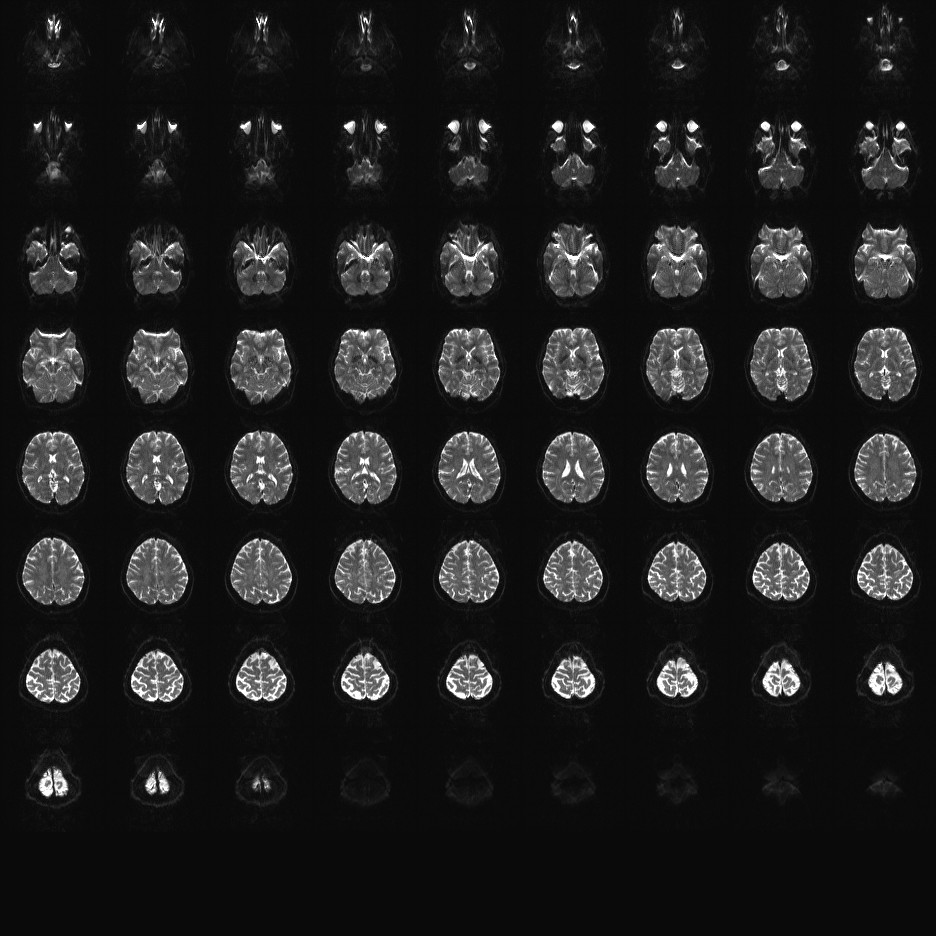

Multi-banded RF pulses can be used to accelerate volume coverage along the slice direction by simultaneously exciting and acquiring multiple slices and subsequently unaliasing them using parallel imaging principles and the spatial information available in multi-channel RF array coils.

This allows for a direct reduction in the volume TR by the number of simultaneously excited slices (i.e., the multiband (MB) factor or the slice acceleration factor).